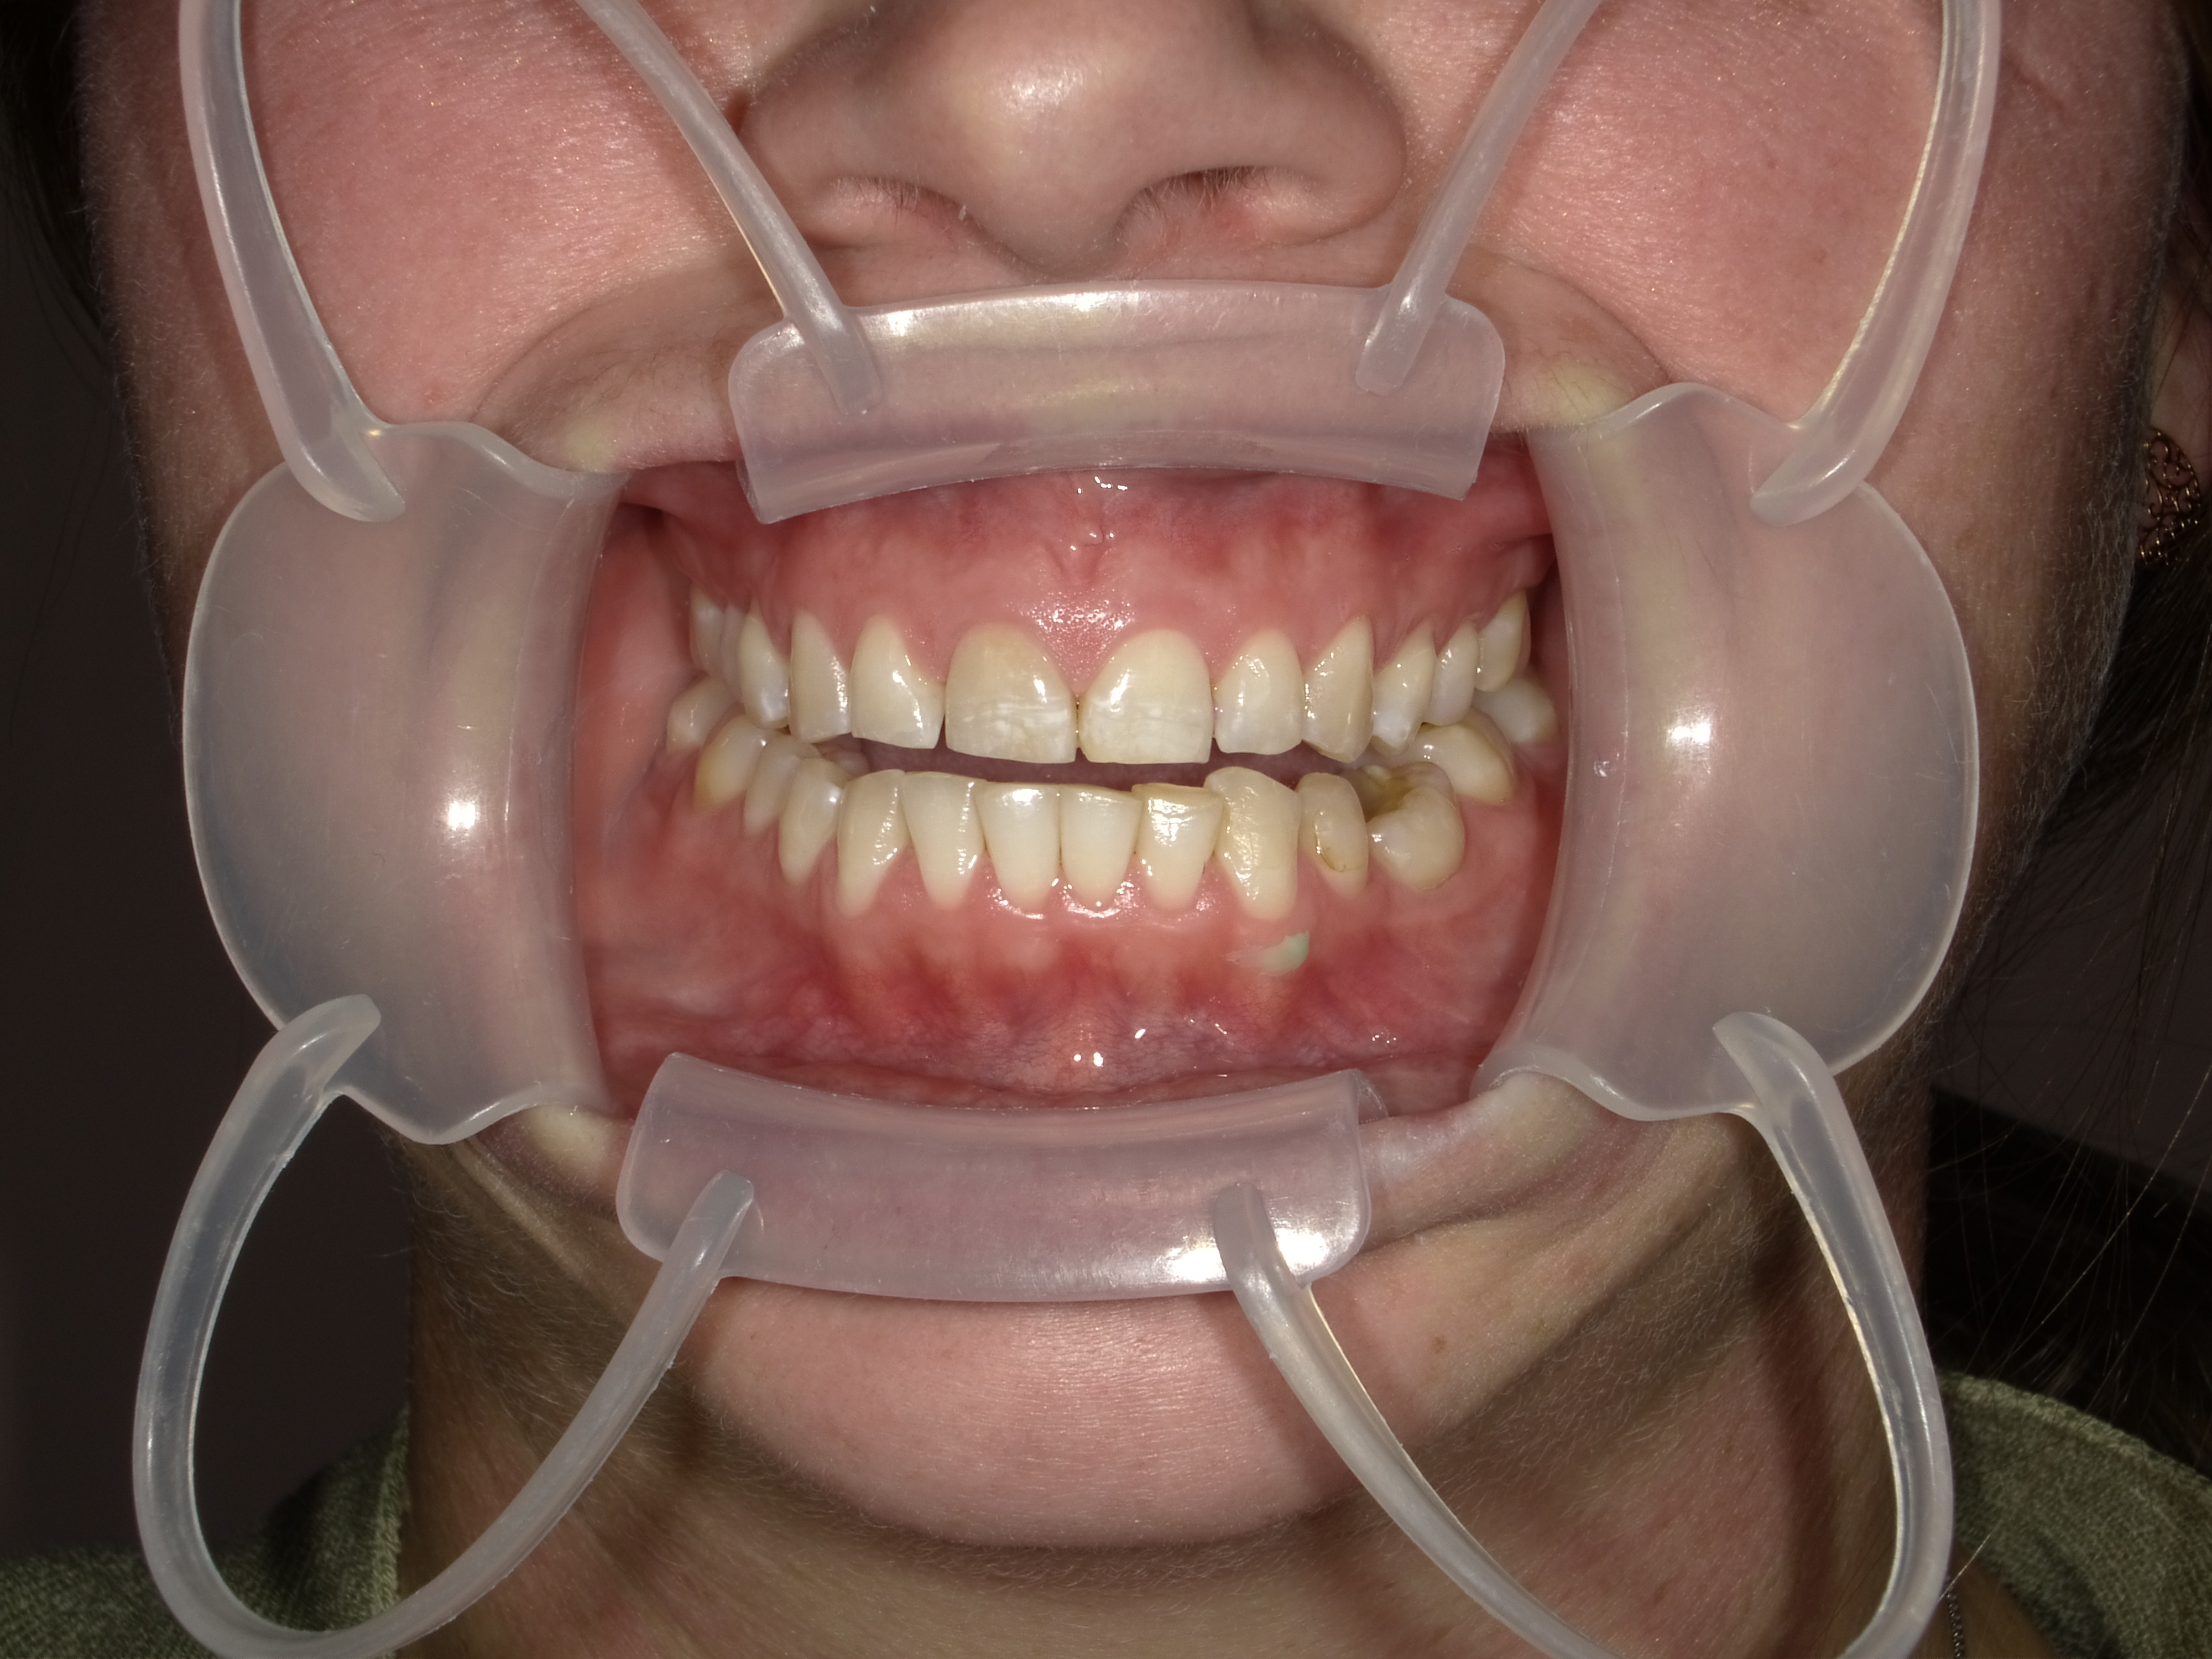

Ideally a retraction system is used for these scans. Two of the best are:

1. The Isolite® retraction system offers control of the patient’s soft tissue and control of saliva, which can interfere with the imaging process. Half of the arch can be scanned, and then the Isolite Mouthpiece can be repositioned and the rest of the dentition captured.

2. The OptraGate® from Ivoclar Vivadent® is indispensable for efficient imaging. I love this product to be in place when taking the photographic records as well. It retracts the lips and keeps the buccal mucosa away back to the first molar. It does this comfortably for the patient, so leaving it in place during the visit is acceptable and speeds up the entire process.

Patient Photographs

At a minimum, 4 photos are required.

1. Front view smile not retracted

2. Front view retracted